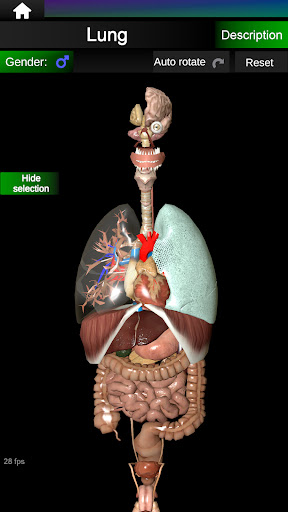

يمكنك هنا تنزيل ملف حزمة تطبيق أندرويد "Internal Organs 3D Anatomy" الخاصة بجهازVodafone Smart N9 Lite مجانًا، نسخة ملف حزمة تطبيق أندرويد - 3.4 للتحميل على Vodafone Smart N9 Lite اضغط ببساطة على هذا الزر. إنه سهل وآمن. نحن نقدم فقط ملفات حزمة تطبيق أندرويد الأصلية. إذا انتهكت أية مواد موجودة في الموقع حقوقك قم بإبلاغنا من خلال